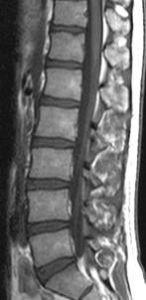

Bei Erkrankungen der Weichteile wie Organe, Muskel, Knorpel oder Gehirn stellt die Kernspintomografie (Magnet-Resonanz-Tomographie, NMR, MRT) die leistungsstärkere, aber auch kostenintensivere Methode dar.

Die Kernspintomografie, auch Magnet-Resonanz-Tomografie (MRT) genannt, ist eine diagnostische Technik zur Darstellung der inneren Organe und Gewebe mit Hilfe von Magnetfeldern und Radiowellen. Tomografie bedeutet Darstellung in Schichten oder Scheiben, in diesem Fall Schichten des Körpers oder eines Körperabschnittes (tomo = lateinisch 'tomus'=griech. 'tomos' eigentlich 'geschnittene Sache'). Mit dieser Methode lassen sich anatomische Abweichungen - zum Beispiel Tumoren oder funktionelle Veränderungen – zum Beispiel Störungen der Durchblutung des Gehirns - im Körper sichtbar machen.

Mit der Magnetresonanztomografie lassen sich Weichteile besonders gut voneinander abgrenzen. Sie werden entsprechend ihres Wasserstoffgehaltes in verschiedenen Graustufen dargestellt. Der kompakte Knochen erscheint dagegen auf dem kernspintomografischen Bild schwarz. Die Methode ist daher besonders aussagekräftig in Körperregionen, in denen viel Weichgewebe vorhanden ist. Sogar eine Unterscheidung zwischen bösartigem und gesundem Gewebe der Weichteile ist hier oft möglich.

Die Kernspintomografie stellt also das bildgebende Verfahren mit der derzeit höchsten Weichteilauflösung dar, so dass sie sich zur Darstellung von Gehirn, Rückenmark oder Muskulatur gleichermaßen gut eignet. Mit Hilfe eines Kontrastmittels kann außerdem Tumor- oder Narbengewebe, das sich z.B. nach einer Operation gebildet hat, hervorgehoben werden.

Wie auch bei der Computertomografie lässt sich der untersuchte Körperabschnitt bei der Kernspintomografie in visuelle Längs- oder Querschichten zerlegen. Allerdings kann man durch Rekonstruktionsverfahren auch dreidimensionale Bilder aus einem MRT-Datensatz herstellen und damit die untersuchten Organe wieder relativ naturgetreu abbilden. Im Vergleich zu manchen anderen bildgebenden Verfahren ist die MRT Untersuchung recht zeitaufwändig. Bis heute ist allerdings auch nach vielen Millionen Untersuchungen keine Nebenwirkung bei Patienten der Kernspintomografie bekannt geworden.